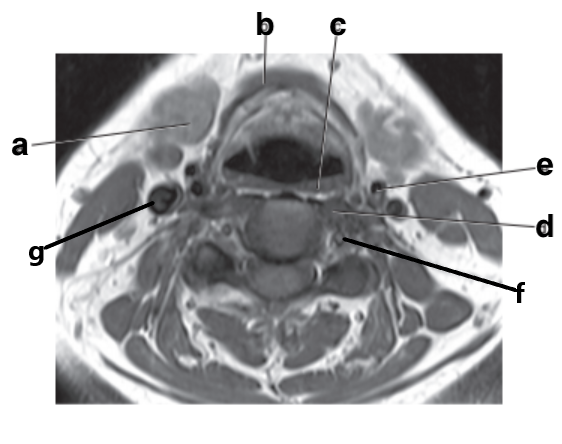

What is letter e?

Subclavian artery

What is letter f?

Vertebral artery

What is letter a?

What is letter b?

Thyroid gland

What is letter c?

Aortic arch

Esophagus

Parotid gland

Trachea

Internal carotid artery

Cervical Spinal cord

Epiglottis

Submandibular gland